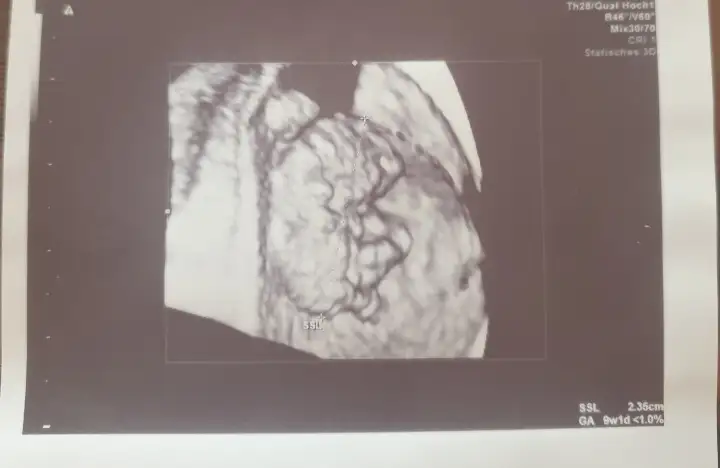

Buda bizim bebis

• 20210511_164603.webp

20210511_164603.webp

24 KB · Görüntüleme: 98

• 20210512_105810.webp

20210512_105810.webp

7,4 KB · Görüntüleme: 84